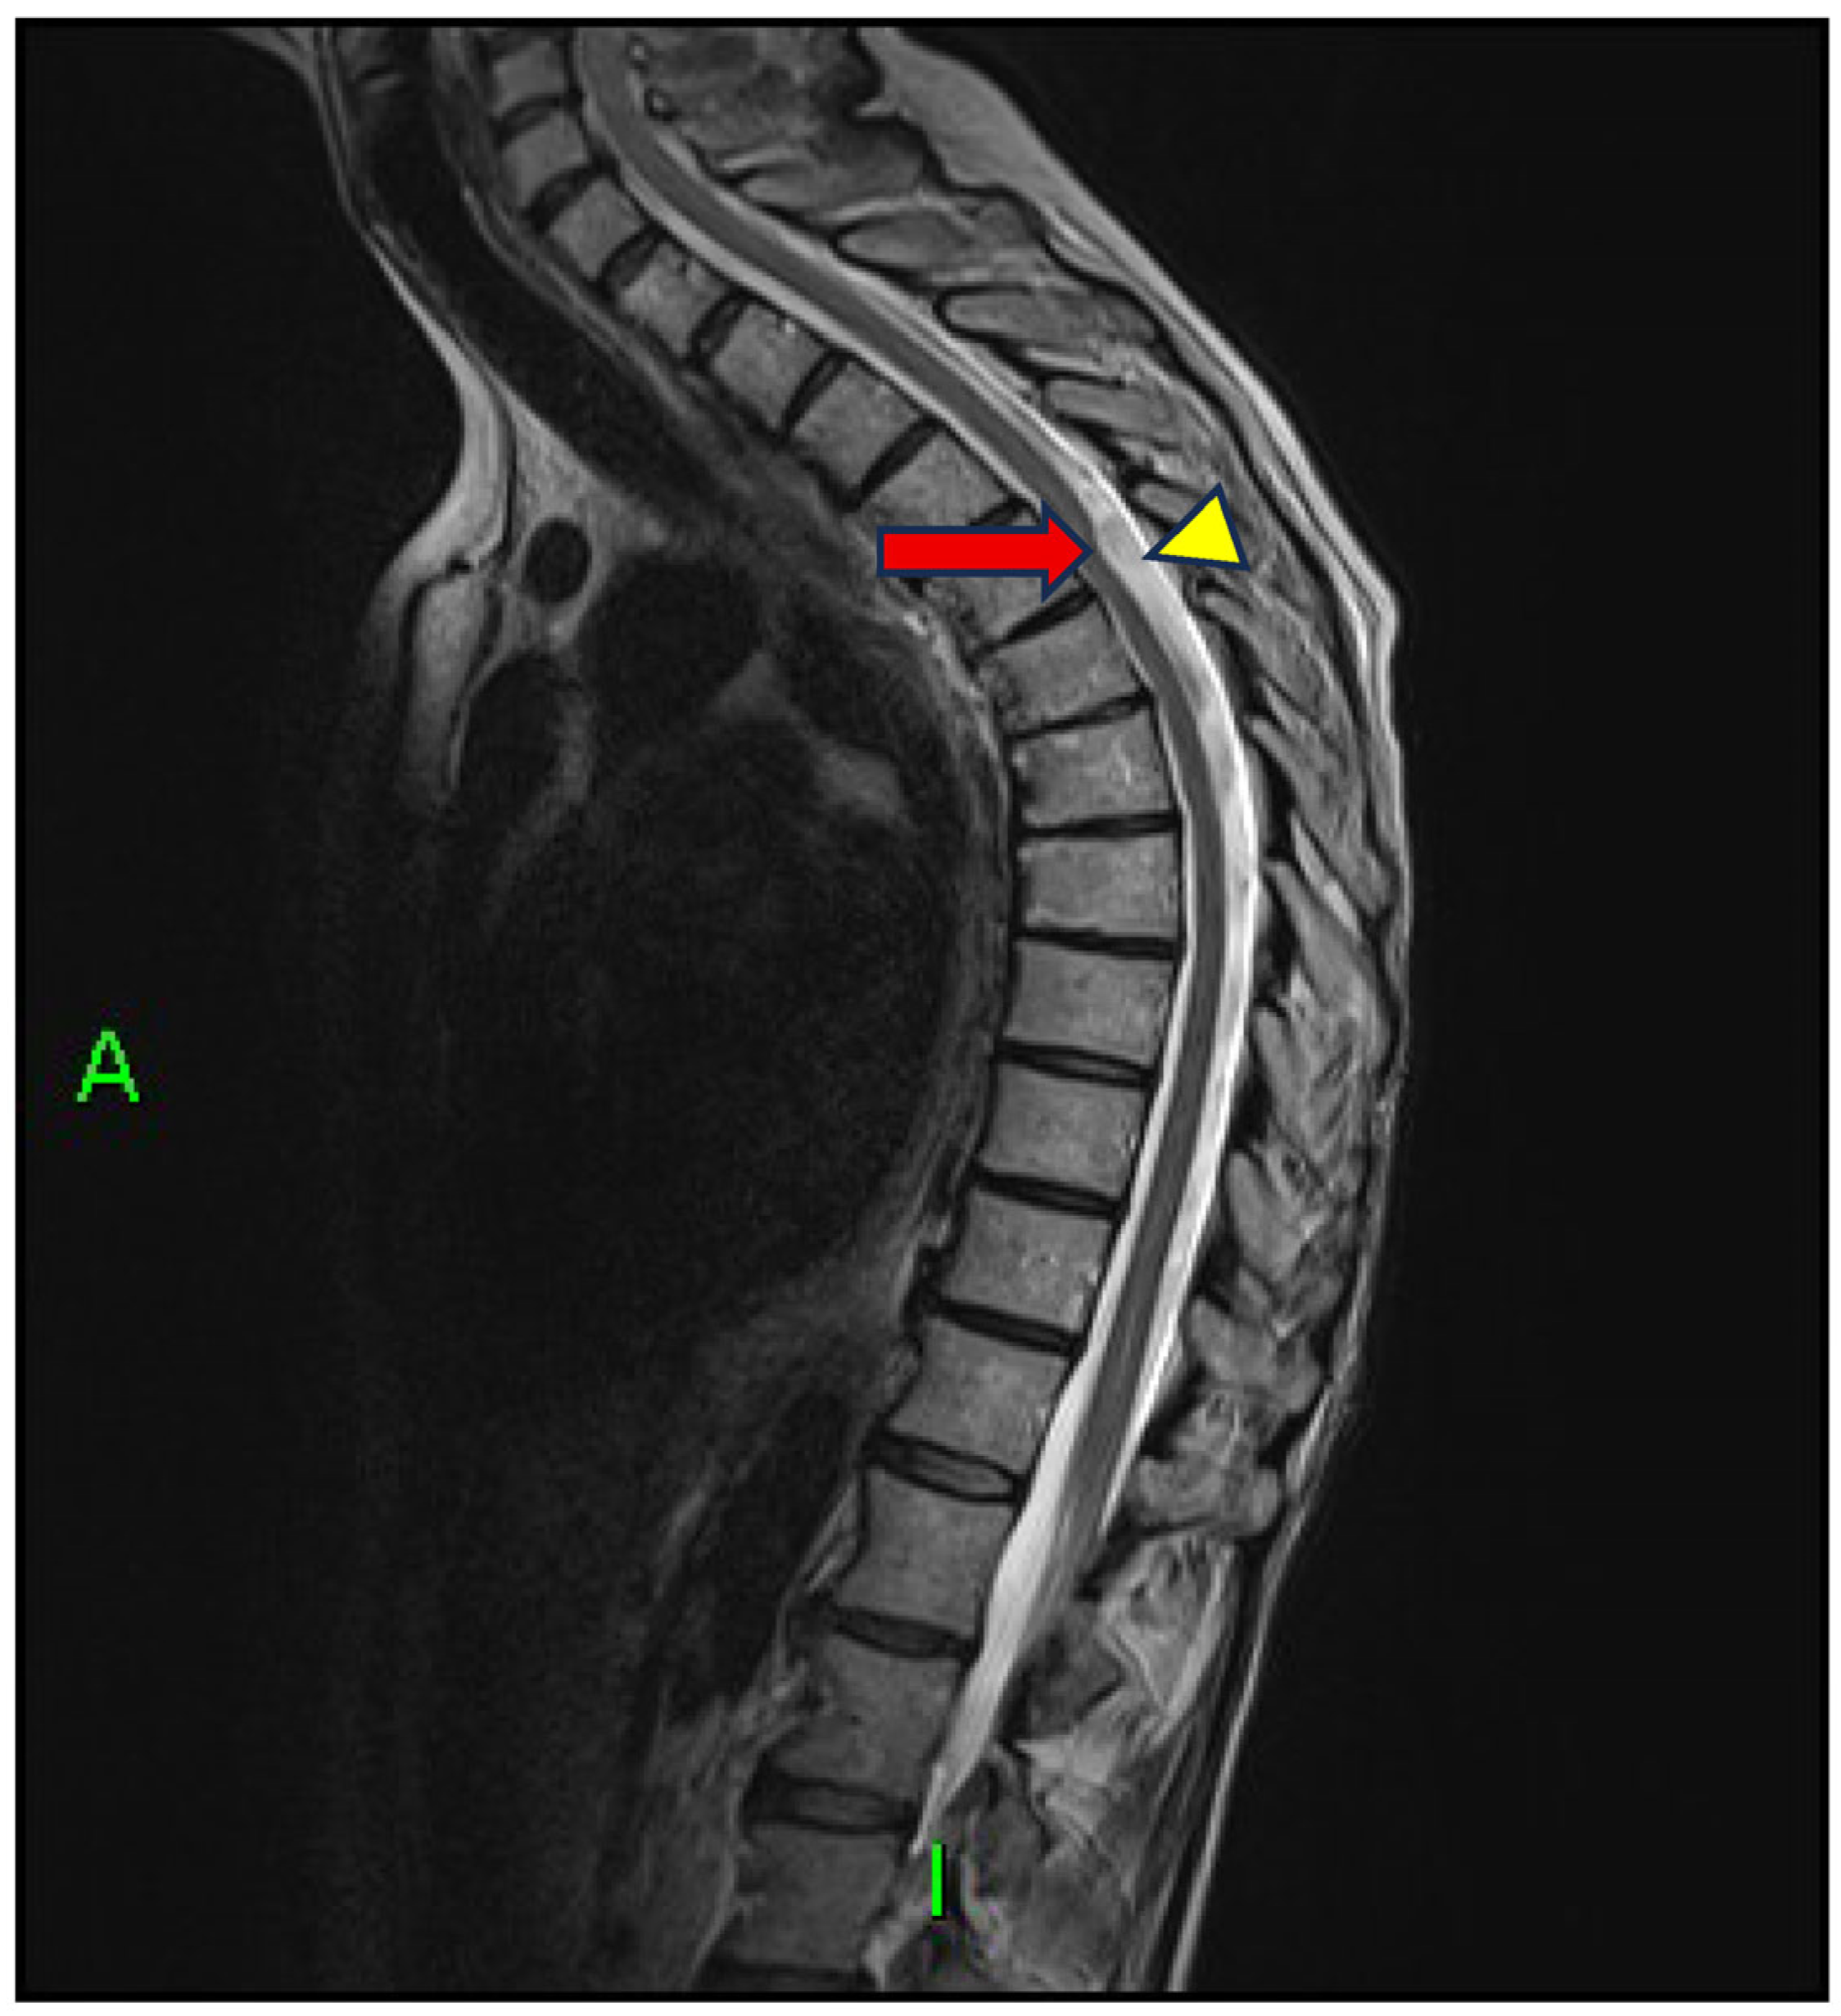

Case Report: Scalpel Sign and Dorsal Arachnoid Cyst—The Importance of an Accurate Diagnosis

1. Introduction and Clinical Significance

2. Case Presentation

3. Discussion